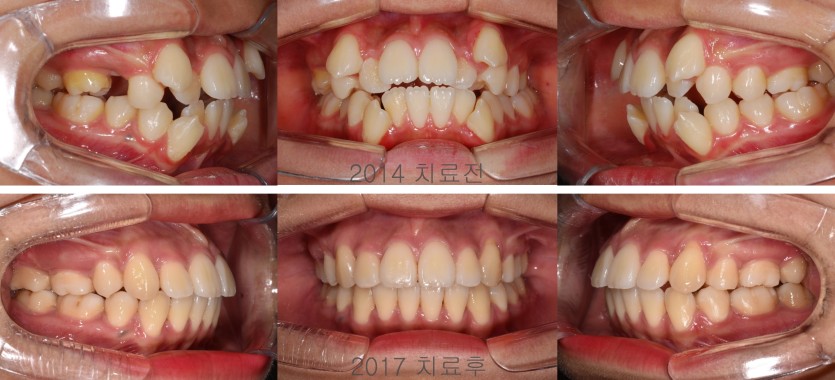

일반적인 덧니 상황에서는 소구치 발치교정치료만으로 상당한 배열공간을 확보할 수 있습니다.  그러나, 상하 대구치간 폭경이 조화롭지 않아 상악 치열을 확장하면서 소구치를 발치해야 하는 경우도 가끔 만납니다. 상악 치조골의 크기가 현저히 작기 때문입니다.  상악을 급속 확장장치로 확장하여 상악 대구치가 하악 대구치를 덮을 수 있도록 만들어주고 발치치아를 재진단하여 발치 교정치료를 진행합니다.  그 역순으로 발치를 먼저하고 후속적으로 대구치 확장을 하는 방법은 적절하지 않습니다.  치료의 순서를 정확히 지키면서 치료해야 합니다.